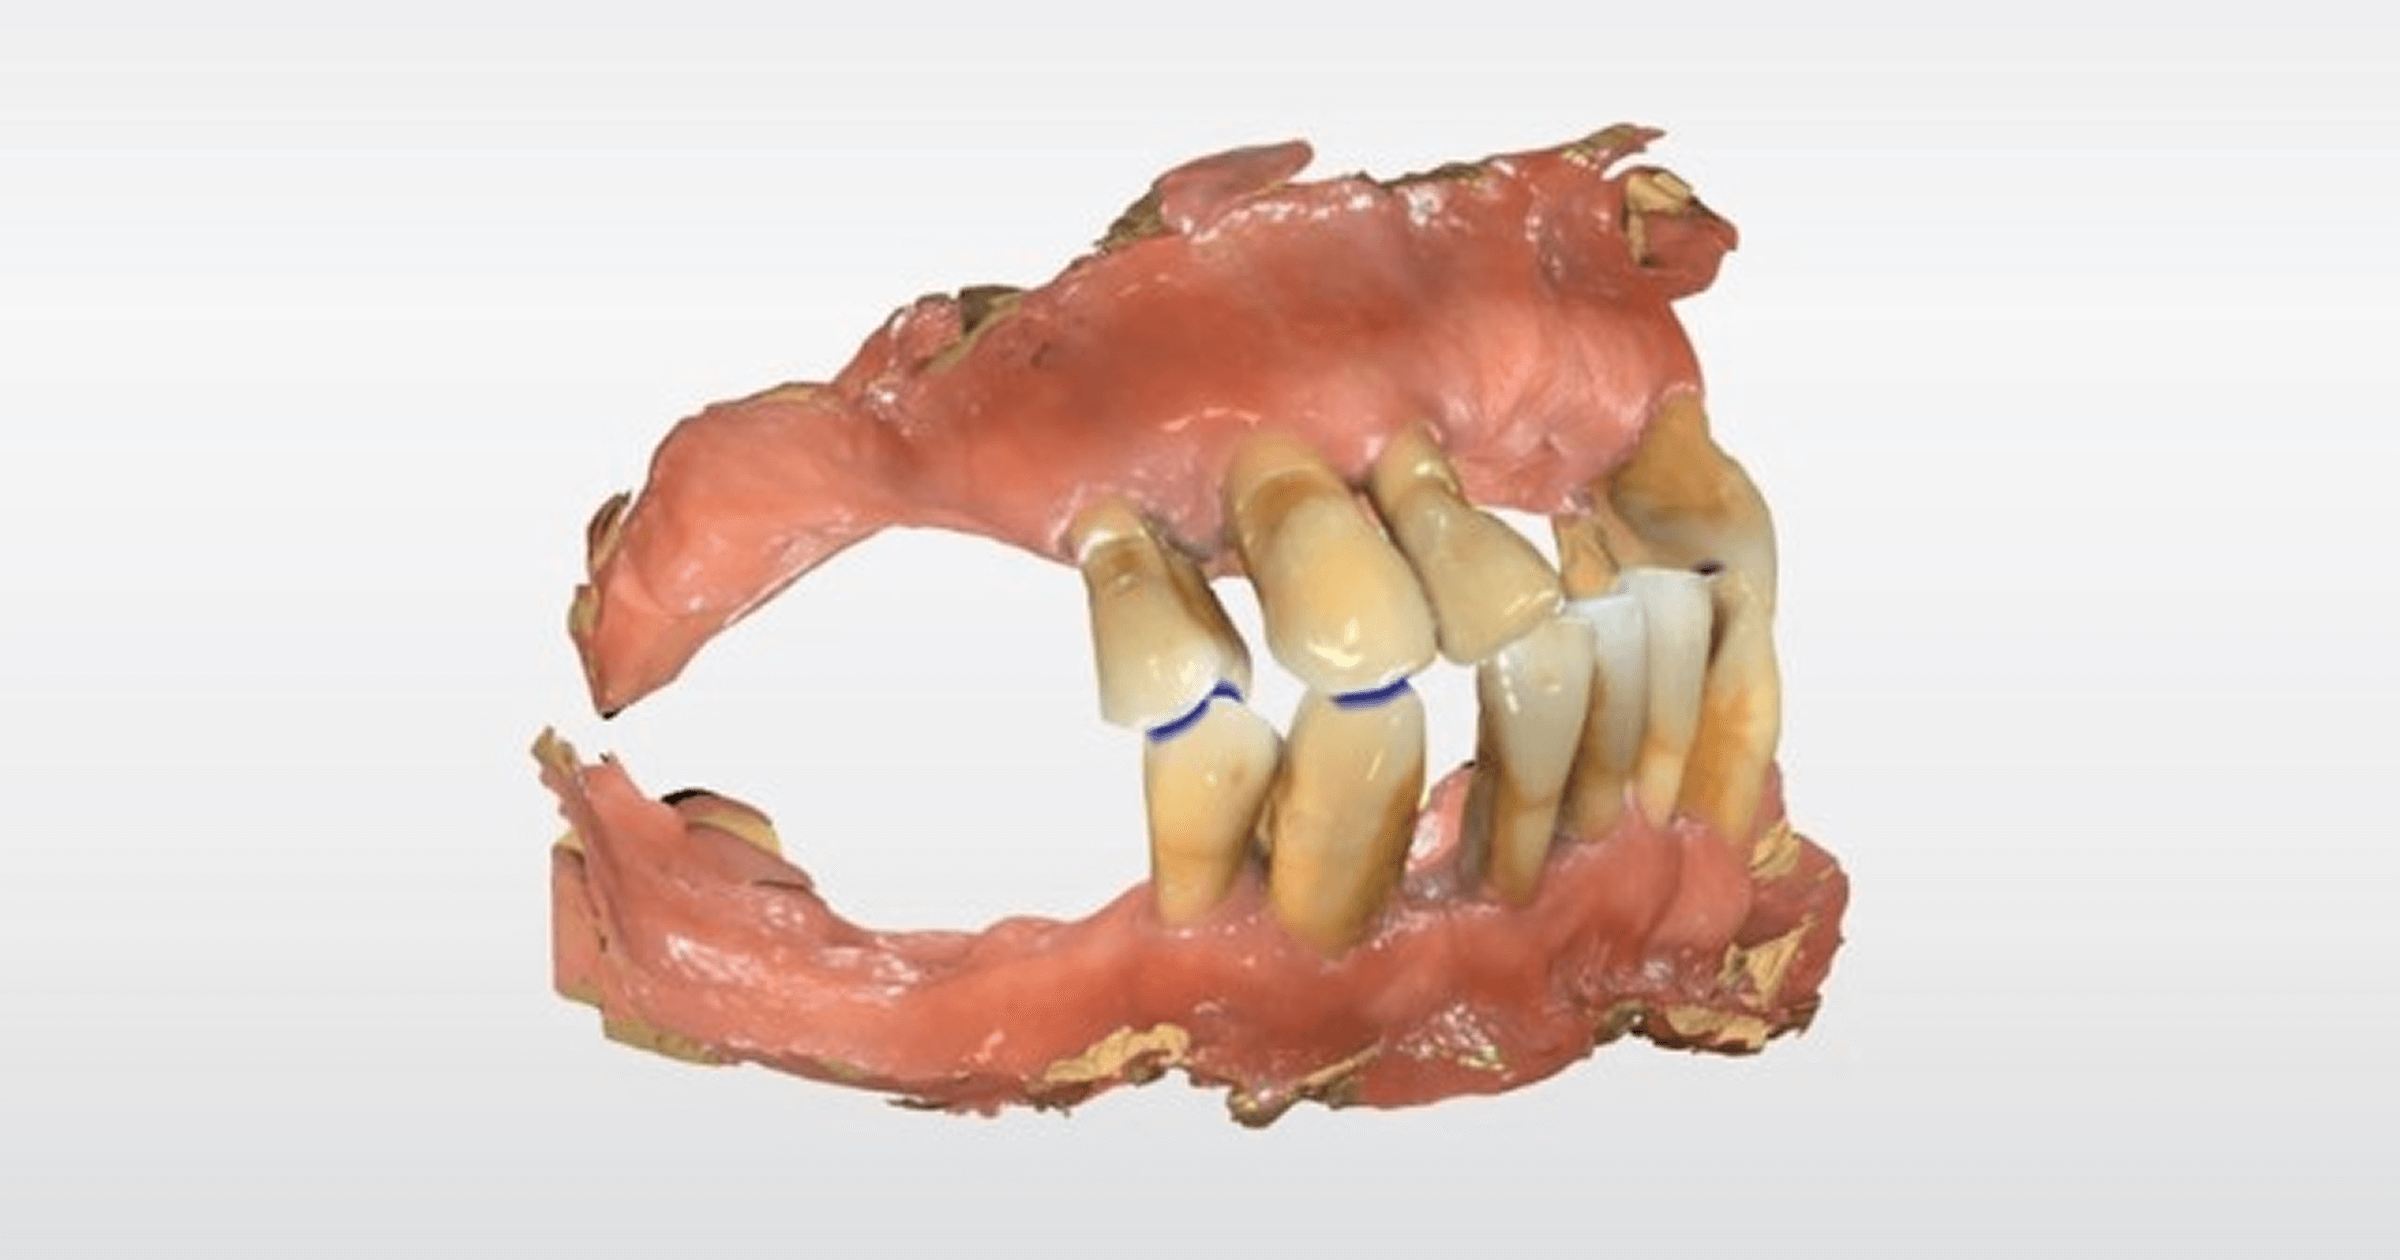

The patient in Figs. 15–20 had existing dentures that were 20-plus years old, so her goal was better-fitting ones with less worn teeth. Interestingly, she was an employee of the lab that had created her dentures! As you can see, they were very worn, and the esthetics could be improved to fill out the buccal corridors and tooth position. And while the fit was reasonable, considering their age, there was also plenty of room for improvement.

This is where things get really cool and take a big turn from an old-school analog process: The patient’s old dentures, which fit somewhat, provided a starting reference point for her new dentures.

- I took a wash impression of the existing dentures, then scanned the impression extraorally, 360 degrees, with a Trios 5 scanner.

In this case, everything was spot-on, except I had missed a small area on the intaglio of one of the old dentures when I did the 360-degree scan of the wash impression. This was easily rectified, however, by simply doing a second wash impression using this try-in and sending it to the lab to be scanned with their desktop scanner. (This has its own advantages because, in situations like this, desktop scanners are less prone than intraoral handheld scanners to introduce errors.) The final dentures (Figs. 22–27) were then fabricated.